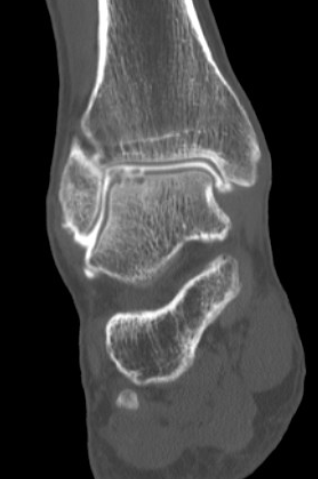

De orthopedisch chirurg zal beslissen of bijkomende onderzoeken nodig zijn (RX, MRI, arthro-CT, SPECT-CT). De grootte, diepte en lokalisatie van een kraakbeenletsel bepalen de behandeling. Een pijnlijk kraakbeenletsel bij de volwassene dient met een ingreep behandeld te worden. Bij kinderen kan een afwachtende houding aangenomen worden, tenzij het bot- kraakbeen-fragment dreigt los te komen: dan is fixatie nodig (of verwijderen als het helemaal is losgekomen).

Indien nodig voert de orthopedisch chirurg een kijkoperatie van de enkel uit (arthroscopie). Via kleine steekgaatjes brengt hij een camera en werkinstrumenten in het gewricht. Het zieke kraakbeen wordt verwijderd en het onderliggende bot wordt voorbereid om het ontstane gat terug op te vullen met “litteken-kraakbeen” (fibro-cartilago).

Grote kraakbeen defecten dienen soms via andere technieken aangepakt te worden. De twee meest toegepaste chirurgische behandelingen bij een groot osteochondraal letsel in de enkel (meestal de talus of sprongbeen), zijn een OATS-procedure en een AMIC-procedure.